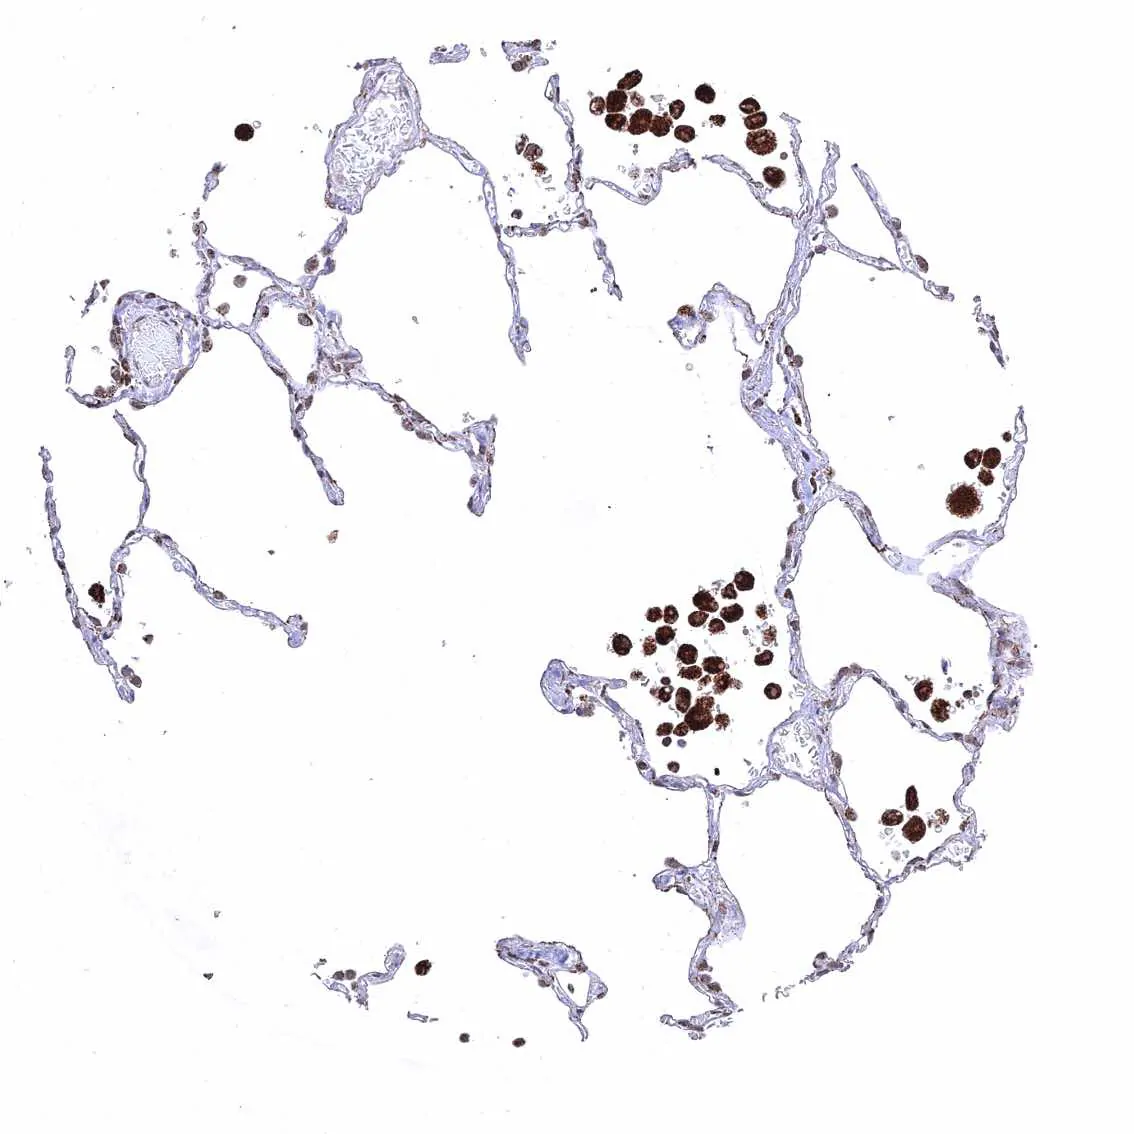

Lung